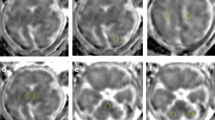

On ex vivo imaging, the apparent diffusion coefficient (ADC) was decreased throughout the WM after 10 days of hypoxia (hypoxia from postnatal day 10 (P10) to P20 and killed at P20 (early hypoxia P20)), corresponding to increased astrocytosis and decreased myelination. Diffusion values normalized after 10 days of normoxia (hypoxia from P10 to P20 and killed at P30 (early hypoxia P30)), but immunohistochemistry revealed significant astrocytosis and hypomyelination. In contrast, ADC and anisotropy were increased after 10 days of hypoxia at a later developmental time point (hypoxia from P20 to P30 and killed at P30 (late hypoxia P30)), with less astrocytosis and more prominent myelination.

Ferrets were subjected to 10% hypoxia and divided into three groups: early hypoxia P20, early hypoxia P30, and late hypoxia P30.